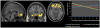

Results: Cumulative adversity was associated with smaller volume in medial prefrontal cortex (PFC), insular cortex, and subgenual anterior cingulate regions (familywise error corrected, p < .001). Recent stressful life events were associated with smaller volume in two clusters: the medial PFC and the right insula. Life trauma was associated with smaller volume in the medial PFC, anterior cingulate, and subgenual regions. The interaction of greater subjective chronic stress and greater cumulative life events was associated with smaller volume in the orbitofrontal cortex, insula, and anterior and subgenual cingulate regions.